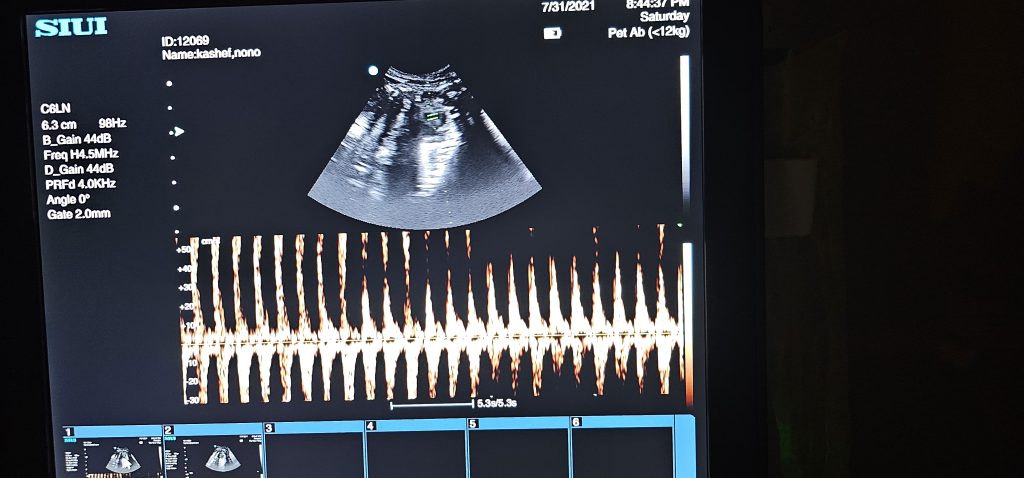

بخش تصویربرداری کلینیک آیرانا با استفاده از دستگاههای پیشرفته رادیولوژی دیجیتال و سونوگرافی تخصصی دامپزشکی، امکان ارزیابی دقیق ساختارهای داخلی بدن حیوانات را فراهم میکند

رادیولوژی برای بررسی مشکلات اسکلتی، قفسه سینه و نواحی شکمی کاربرد دارد و سونوگرافی، بهصورت مکمل، در تشخیص بافت نرم و ارزیابی اندامهایی مانند کبد، کلیه، معده، روده، رحم و مثانه نقش کلیدی دارد.

ترکیب این دو روش، تشخیص سریعتر و دقیقتر را برای تیم درمانی ممکن میسازد